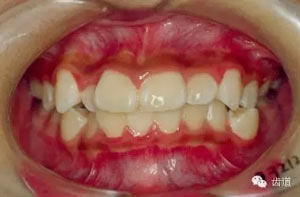

5.齲齒、牙周病及口腔衛(wèi)生情況。

45.webp.jpg